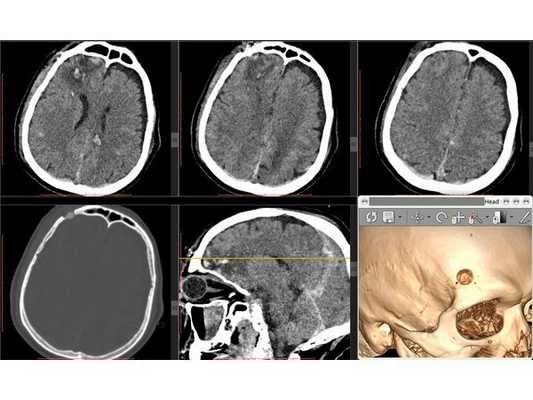

КТ головного мозга в первые сутки: выявлен линейный перелом лобной кости, переходящий на основание передней черепной ямки, и очаги ушиба полюсных отделов правой височной и лобной долей головного мозга (II вид по Корниенко), травматическое субарахноидальное кровоизлияние. Также выявлен двусторонний перелом нижней челюсти. КТ головного мозга на вторые сутки: выявлена трансформация очага ушиба правой лобной доли во внутримозговую гематому (агрессивный очаг ушиба головного мозга).

КТ головного мозга на вторые сутки: отсроченное формирование внутримозговой гематомы в правой лобной доле

После операции состояние пациента постепенного восстановилось до ясного. На третьи сутки после операции проведена контрольная КТ головного мозга. Также пациент был оперирован по поводу скелетной травмы, деканулирован на восьмые сутки после операции. Операционная рана и трахеостома зажили.